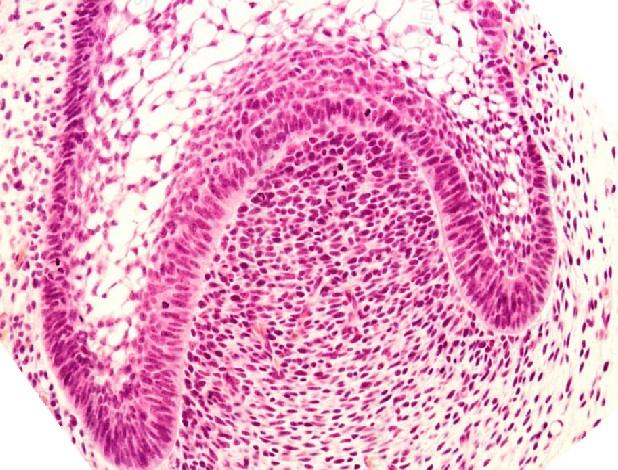

High-quality histology and staining are foundational to understanding tissue architecture, cellular behavior, and materialโ€“tissue interactions at the microscopic level. Histology & Staining Services enable detailed evaluation of biological response, biocompatibility, inflammation, integration, and structural organization across native tissues, engineered constructs, and biomaterials.

Histology reveals tissue structure, cellular organization, inflammation, fibrosis, vascularization, and biological response. Staining methodsโ€”including H&E, Masson’s Trichrome, PAS, Alcian Blue, IHC, and IFโ€”highlight essential features for evaluating biocompatibility and functional performance.

Paraffin-embedded tissue block being trimmed and prepared for microtome sectioning.

Stained tissue section showing cellular morphology under brightfield microscopy.